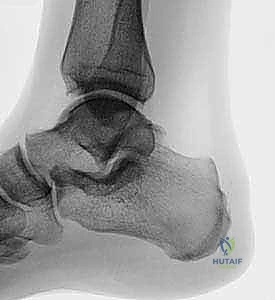

2. التصوير بالأشعة السينية (X-Rays)

تُعد الأشعة السينية العادية (خاصة الوضع الجانبي - Lateral View) الخطوة التصويرية الأولى والأهم. تظهر الأشعة بوضوح عظم العقب والنتوء العظمي (نتوء هاغلوند). يقوم الدكتور هطيف بإجراء قياسات هندسية دقيقة على صور الأشعة، مثل حساب زاوية "فاولر-فيليب" (Fowler-Philip Angle) وخطوط الميل المتوازية (Parallel Pitch Lines). هذه القياسات العلمية الدقيقة تساعد في تأكيد ما إذا كان بروز العظم يتجاوز الحدود الطبيعية ويشكل ضغطاً ميكانيكياً حقيقياً. كما تكشف الأشعة عن وجود أي تكلسات أو نتوءات عظمية داخل وتر أخيل نفسه.